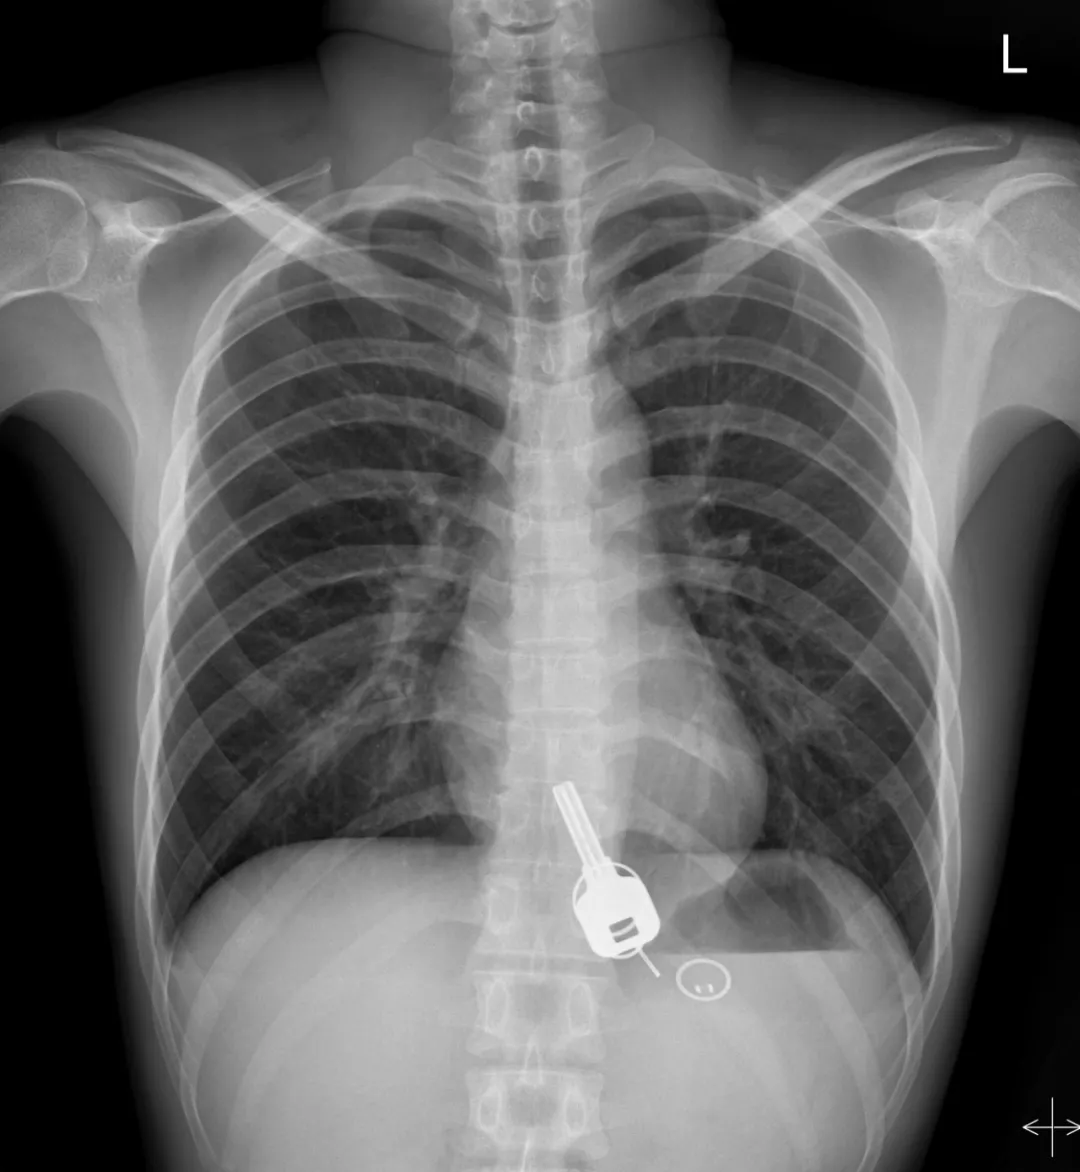

广东东莞的常先生酒后回家找不到钥匙,酒醒后他感到胸口疼痛,去医院一查,发现一把铁钥匙、2个钥匙扣、1个门禁牌清楚显示在肚子胃区的位置上。

医生准备在胃镜下取出钥匙,不料,因钥匙太大在常先生喉咙附近食管入口处卡住了,取不出来,最后,医生决定给常先生做无痛胃镜,麻醉后,常先生食管入口处肌肉松弛,钥匙终于顺利取出!。